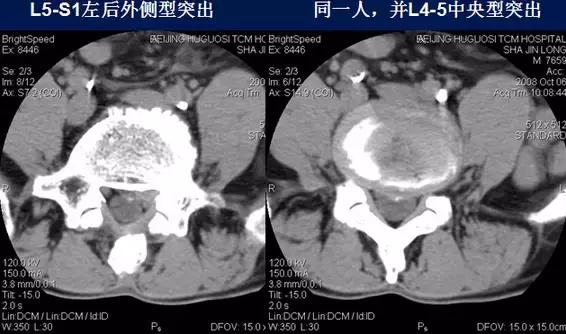

椎间盘突出:

⑴中央型:椎间盘影局限性超出椎体边缘,硬膜囊可受压,硬膜外脂肪间隙变窄、消失,可伴纤维环钙化。

⑵旁中央型:椎间盘影局限性超出椎体边缘,神经根受压。

⑶后外侧型:椎间盘影于椎间孔方向局限性超出椎体边缘,神经根受压,椎间孔、侧隐窝变窄。

硬膜外脂肪间隙变窄、消失,可伴纤维环钙化。

⑷远外侧型:椎间盘影于椎管外局限性超出椎体边缘,多伴纤维环钙化,骨赘形成,脊神经、周围肌肉、韧带受压移位。